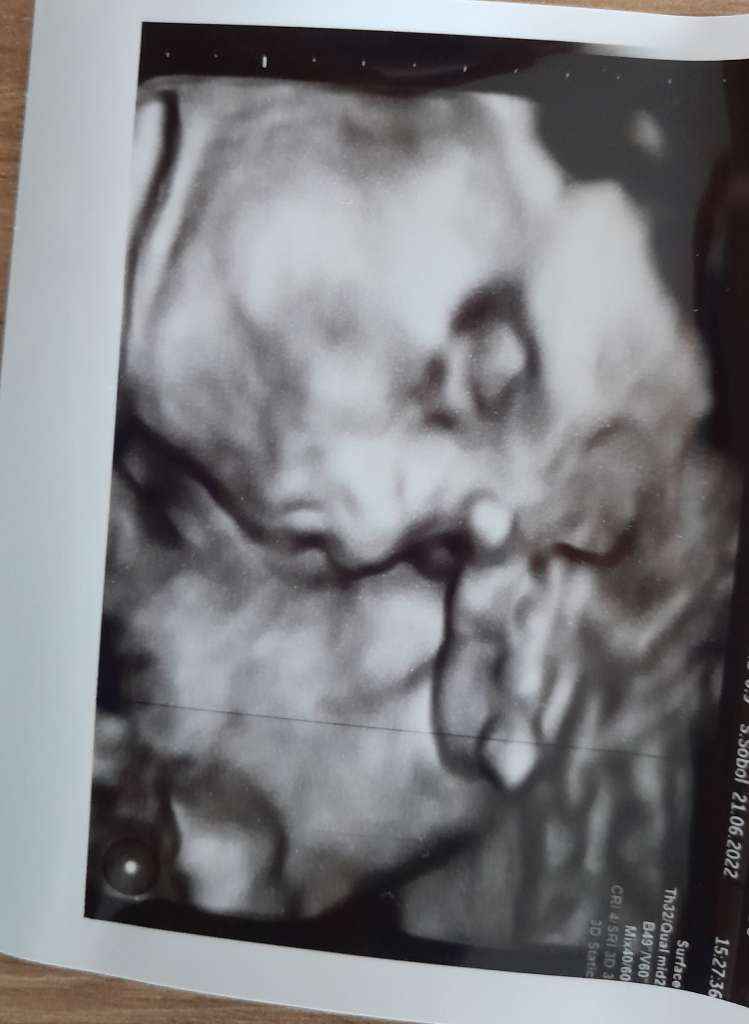

wizyta ok, mały rosnie( choc pomiary dopiero za 4tyg), szyjka długa, łożysko wysoko więc wygląda wszystko dobrze🙂 juz bardziej czlowieka przypomina haha